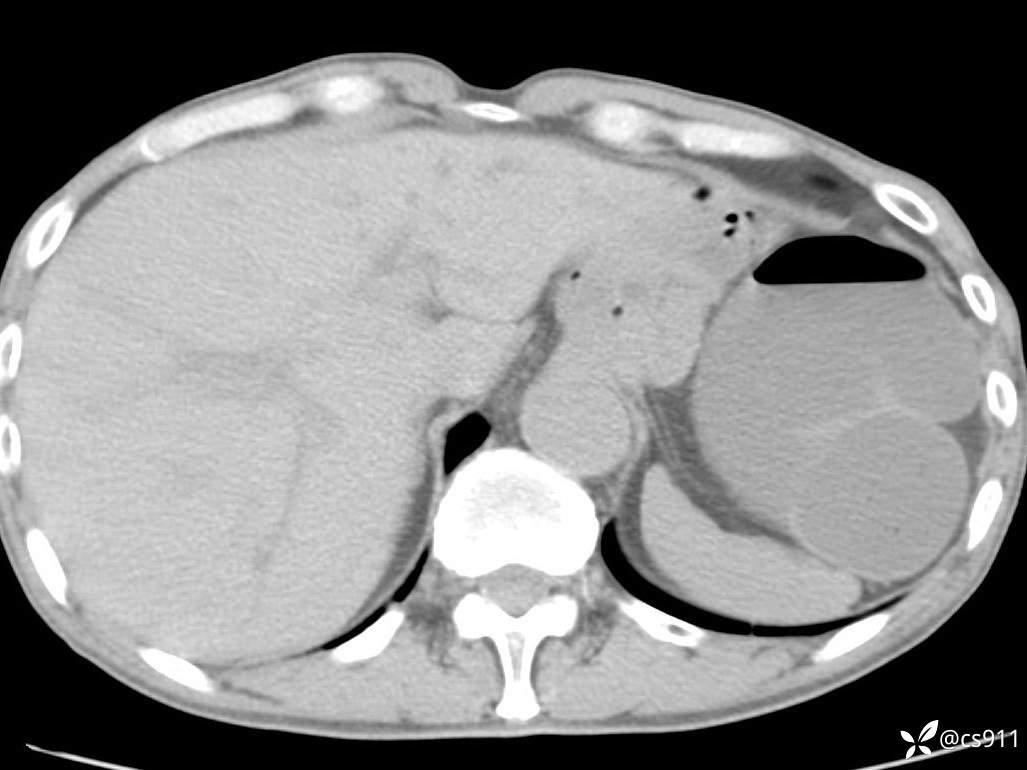

急腹症之急诊CT,原因?答案公布

男,77岁,腹痛、腹胀伴恶心呕吐1天。呕吐胃内容物,非喷射性呕吐,有咖啡色样胃内容物,诉有胃穿孔病史。查体:全腹平,下腹部压痛,全腹无反跳痛,叩诊呈浊音,移动性浊音阴性,肠鸣音减弱,1-2次/分。肛检:直肠未扪及明显肿物,可触及大量粪块。

血淀粉酶(AMY) HH 1859 U/L 35-135

癌胚抗原(CEA) H 27.44 ng/ml 0-5